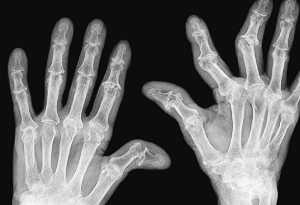

3. 관절 부음

류마티스 관절염은 주로 양쪽의 대칭적인 작은 관절을 표적으로 합니다. 손가락, 발가락의 관절, 손목, 발목, 팔꿈치, 무릎 등이 부어오르고 아프며 따끔거립니다. 이런 부음은 염증으로 인해 관절 주변의 활막이 팽창하고 관절액이 증가하기 때문입니다.

6. 부종

평소보다 몸이 부은 것 같은 느낌이 들면 류마티스 관절염을 의심해 볼 수 있습니다. 특히 신발이 갑자기 맞지 않거나 손마디가 부었다면 이 질환을 의심해 볼 필요가 있습니다.